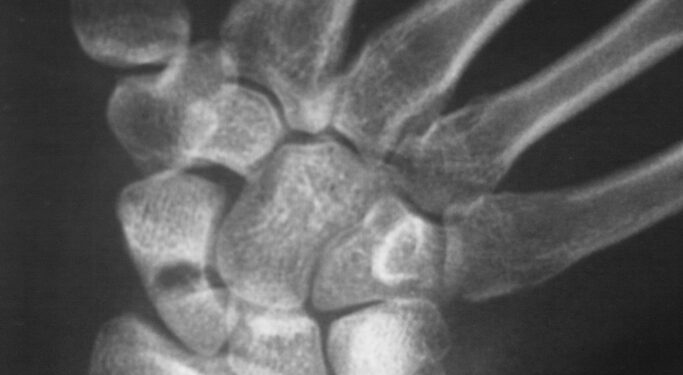

Dilbio srityje yra dvi pagrindinės kaulo struktūros – stipinkaulis ir alkūnkaulis. Alkūnkaulis prasideda ties riešo išorine dalimi, o stipinkaulis – vidine. Ties alkūnkaulio galu, prie pat plaštakos, susiformavęs kaulinis išsikišimas, vadinamas alkūnkaulio pentine atauga. Ji įsitvirtina riešo sąnario kremzlėje ir užtikrina riešo tvirtumą bei lankstumą. Kai šioje vietoje įvyksta lūžis, jis vadinamas alkūnkaulio pentinės ataugos lūžiu.

Dažniausias alkūnkaulio pentinės ataugos lūžio požymis – staigus skausmas. Paprastai šis lūžis būna kartu su stipinkaulio lūžiu, todėl neretai jaučiamas skausmas ne šalia alkūnkaulio ataugos, o arčiau stipinkaulio – riešo vidinėje pusėje.

Alkūnkaulio pentinės ataugos lūžiai dažniausiai įvyksta, kai krentant bandoma atsiremti ištiesta ranka. Tai labiausiai paplitęs riešo bei rankos kaulų lūžių priežastis.

Lūžusius kaulus būtina tinkamai sugrąžinti į pradinę padėtį ir užfiksuoti, kad jie galėtų suaugti. Priklausomai nuo lūžio sudėtingumo, taikomi skirtingi gydymo būdai.

Nesmarkiam lūžiui paprastai pakanka riešo imobilizacijos – riešas sutvirtinamas specialiu gipsu ar įtvaru. Kartais prieš tai kaulai sulygiuojami, vadinama kaulų repozicija, kuri kai kuriais atvejais atliekama be pjūvio.

Jei lūžis sudėtingas ar pažeisti kiti šalia esantys kaulai, dažnai reikalinga chirurginė operacija. Šiuo atveju gydytojas padaro pjūvį, sugretina kaulus ir naudoja metalinius varžtus ar kaiščius, kad fragmentai tinkamai sugijtų. Po operacijos dedamas tvirtas gipsinis arba stiklo pluošto įtvaras.